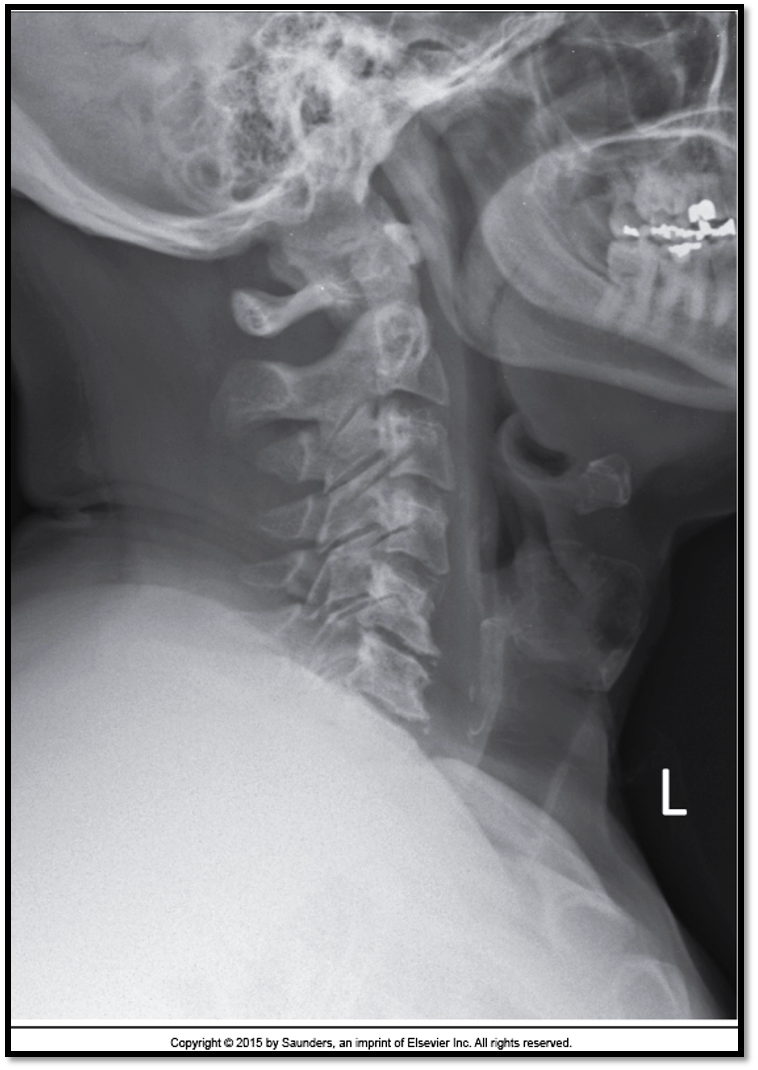

Lateral Cspine Criteria

• SI’d articular pillars and open zygopophyseal joints

• superimposition of posterior vertebral bodies

• mandible off spine

• open intervertebral spaces